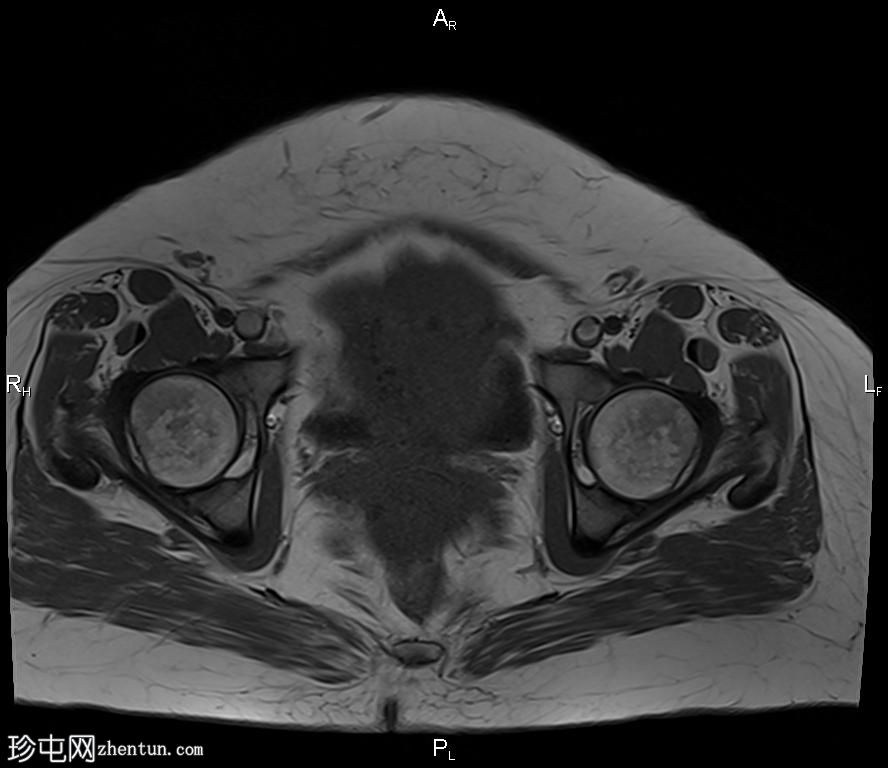

轴向T2

脂肪饱和度

盆腔内可见一巨大多分叶实性肿块,内部有隔膜,T2WI信号不均匀,T1WI信号不均匀,呈低信号。肿块内散在分布囊性/坏死性病变。

肿块外可见子宫和右侧卵巢,肿块似源自左侧卵巢。该肿块压迫膀胱和两侧远端输尿管,并导致肠管和血管结构移位,但无侵袭或包裹征象。

造影后,肿块呈不均匀强化,隔膜强化。

远端髂腹旁和两侧髂骨旁区域可见少量肿大淋巴结。